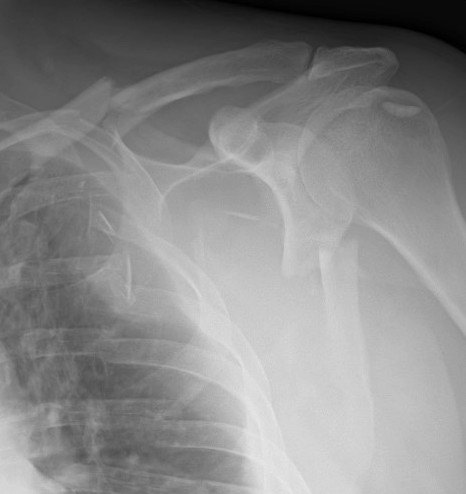

Scapular neck fracture with clavicle fracture